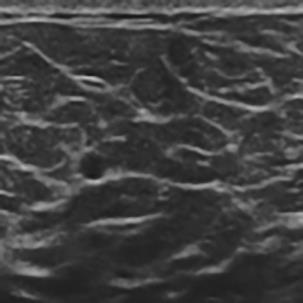

基于逐通道空间自适应选择核卷积与双向边界感知机制的乳腺超声图像病变分割网络

A Breast Ultrasound Images Lesion Segmentation Network Based on Channel-Wise Spatially Adaptive Selective Kernel Convolution and Bidirectional Boundary-Aware Mechanism

乳腺癌是全球女性最常见的恶性肿瘤之一,准确的病变分割对于乳腺癌的早期诊断与治疗具有重要意义。然而,由于病变形态的多样性以及超声成像机制的复杂性,现有基于深度学习的乳腺超声图像病变分割方法在分割准确性方面仍面临巨大挑战。为进一步提升乳腺超声图像中病变区域的分割精度,该文基于经典U-Net架构,提出了一种新型乳腺超声图像病变分割网络(CWSASKM-BBAM-Net)。首先,在网络中引入逐通道空间自适应选择核卷积模块(CWSASKM),根据不同通道的语义特征为每个空间位置自适应选择感受野大小,以增强多尺度信息的建模能力;然后,引入双向边界感知机制(BBAM),通过融合正向与反向注意力,对目标显著区域及其边界进行协同建模,同时逐步提升对非显著区域与病变区域的区分能力,以进一步强化边界信息的表达;最后,在3组公开乳腺超声图像数据集(BUSI、UDIAT和STU)上开展分割实验。结果表明:该方法在数据集BUSI上的杰卡德指数、精确率、召回率和Dice相似系数分别为71.97%、82.85%、81.40%和80.44%,较次优方法分别提升1.69、1.05、1.28和1.84个百分点;在数据集UDIAT上,这4项指标分别达到78.14%、88.31%、86.73%和86.10%,较次优方法分别提升了2.75、2.04、0.56和2.01个百分点;在外部数据集STU上,该方法也取得了优于其他方法的整体表现。实验结果表明,CWSASKM-BBAM-Net在乳腺超声图像分割任务中展现出更优的整体性能。